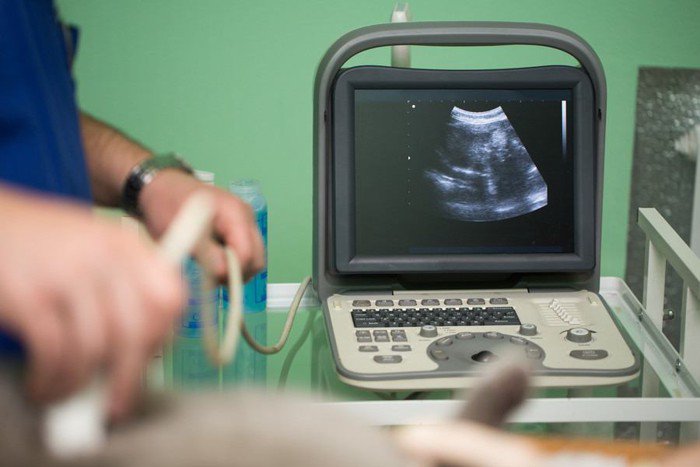

レントゲンや超音波などの画像検査

腎臓の形や状態を詳しく知るために、画像検査をおこないます。

腎臓の大きさに左右差がないか、嚢胞が出来ていないか、腫瘍がないかなどを調べます。

腎機能をはかるために、造影検査をおこなう場合もあります。

腎臓病には急性腎臓病というものもあり、

腎盂腎炎や腎結石などによる障害、腫瘍などの場合には原因を適切に治療することで腎機能の回復が望める場合もあるため、画像検査は欠かせません。